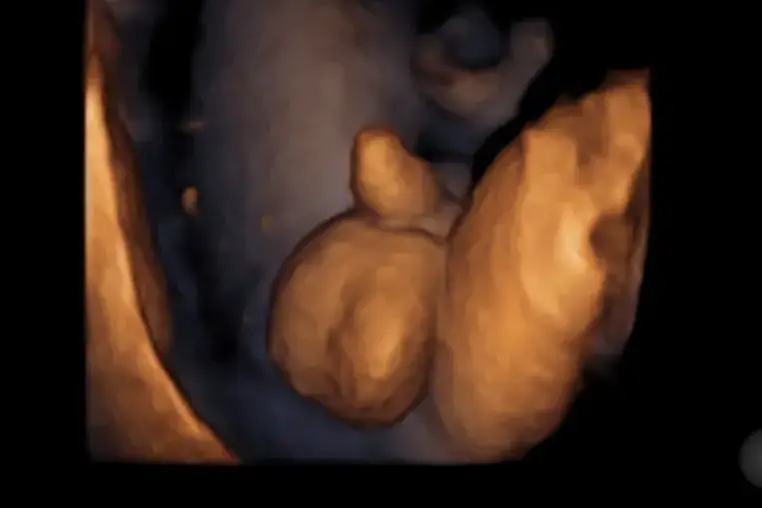

Ultrasonografia (USG) w pierwszym trymestrze ciąży to istotne badanie, które pozwala na ocenę rozwoju płodu. W tym okresie, lekarz może zobaczyć zarodek oraz jego podstawowe struktury, takie jak serce, które zaczyna bić już około 6. tygodnia. Możliwe jest również zauważenie guzków płciowych, co umożliwia wstępne określenie płci dziecka, jednak dokładność w tym czasie wynosi jedynie 75-90%. Warto zaznaczyć, że precyzja tego badania zależy od wielu czynników, takich jak ułożenie płodu, jakość sprzętu oraz doświadczenie specjalisty.

USG w drugim trymestrze: najlepszy czas na potwierdzenie